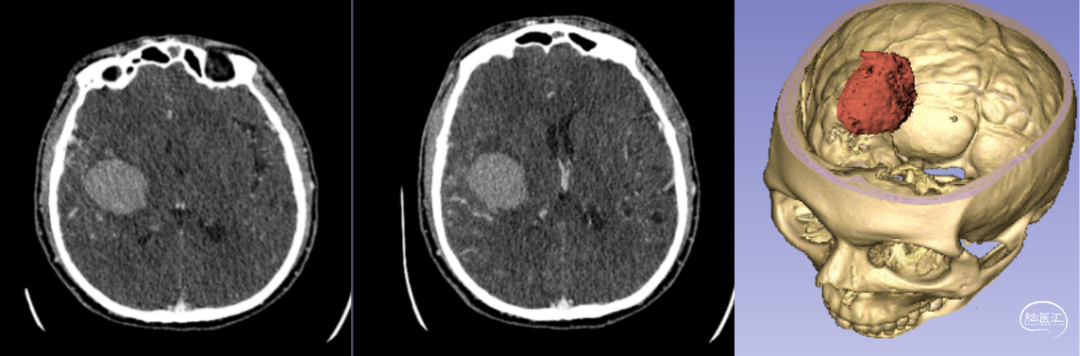

新疆醫科大學(xué)第一附屬醫院神經(jīng)外科中心已成功將該技術(shù)應用于多例腦卒中患者的治療。以一例典型病例為例:[14]

- 患者情況:52歲女性,因“右側肢體無(wú)力1天”就診,入院時(shí)呈淺昏迷狀態(tài),雙側瞳孔等大等圓(直徑約3.5mm),對光反射遲鈍,右側肢體肌力為0級。

- 手術(shù)過(guò)程:基于術(shù)前影像數據,團隊利用3D打印技術(shù)設計并制作個(gè)性化手術(shù)導板,精準定位血腫位置后實(shí)施穿刺引流。術(shù)后復查頭部CT顯示,引流管準確位于血腫腔內,血腫清除效果良好。